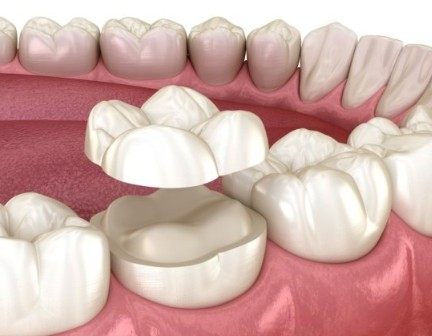

오버레이(Overlay)는 치아의 모든 면을

삭제하는 크라운과 다릅니다.

『 오버레이(Overlay)는

씹는면(교합면)을 적절하게 삭제하고

도자기 재료를 치아에 접착해 주는 방법 』

치료할 범위가 작다 → 인레이

치료할 범위가 좀 더 크다 → 온레이

치료할 범위가 치아의 씹는면을 덮는다 → 오버레이

오버레이를 접착한 모습입니다.

꼭 크라운처럼 보이네요. 감쪽같습니다.